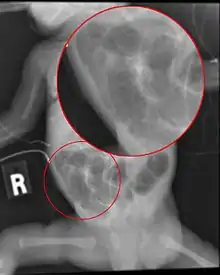

Diagnosis is usually suspected clinically, but often requires the aid of diagnostic imaging, most commonly radiography, which can show the intestines and may show areas with death tissue or a bowel perforation.[19] Specific radiographic signs of NEC are associated with specific Bell's stages of the disease:[20]

- Specific radiologic signs (pneumatosis intestinalis or portal venous gas)

- Severe radiologic signs (pneumoperitoneum)

Alimentary tract of infant showing intestinal necrosis, pneumatosis intestinalis, and perforation site (arrow) (autopsy)

Close-up of intestine of infant showing necrosis and pneumatosis intestinalis (autopsy)